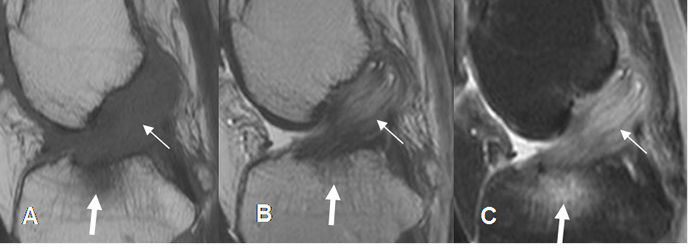

Fig 94. Ruptura aguda del LCA.

A: RM sagital en T1, B: RM sagital en T2 y C: RM sagital en STIR. No visualización del LCA, con cambios inflamatorios agudos, por ruptura reciente.